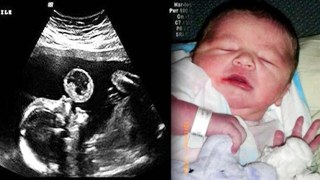

แม่ใจสลาย !! หมออัลตร้าซาวด์ เห็นสิ่งนี้บนปากทารกน้อย หมอเลยให้ทำแท้ง สุดท้ายออกมาเป็นแบบนี้